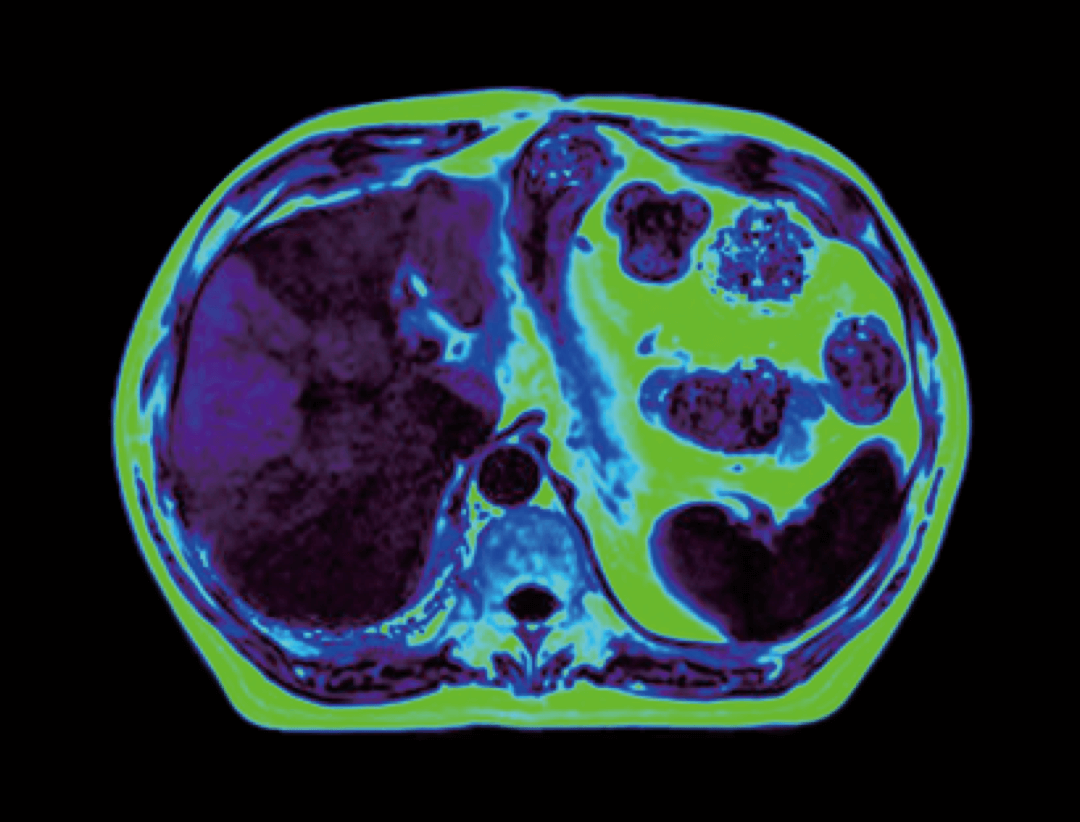

智云平台

智云磁体

自主研发的匀场技术,优异的磁场均匀度。

智云梯度

智能涡流补偿技术,高梯度性能。